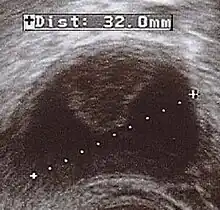

Corpus luteum cyst with bleeding. Fresh blood is anechoic (black). A protrusion of coagulated blood (lighter in color) can also be seen in the top of the cyst. | |